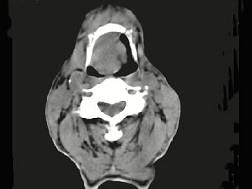

问题 男,74岁,咽喉部不适一年余,近两三个月咽喉疼痛,吞咽困难,CT如图所示,最可能诊断是 ( )

选项 A、声门下区癌 B、跨声门型癌 C、会厌癌 D、声带癌 E、喉癌

答案 C